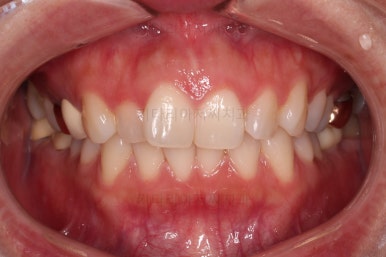

전후 사진을 비교해 볼게요.

6개월만에 부산부분치아교정 완료했어요.

치열도 가지런해졌고, 웃는 모습도 매우 좋아졌네요.